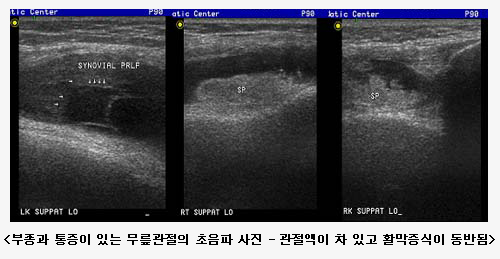

°üÀý ÃÊÀ½ÆÄ Ŭ¸®´Ð |

Ãâó : ·ù¸¶Æ¼½º³»°ú - È«½ÂÀç ±³¼ö ÃÖÁ¾¼öÁ¤ : 2004.11.15 ÀÔ·Â: 2004.11.15 |

°æÈñÀÇ·á¿ø ·ù¸¶Æ¼½º ³»°ú¿¡¼´Â ±Ù°ñ°Ý°è ÃÊÀ½ÆÄ¸¦ ÀÌ¿ëÇÏ¿© ·ù¸¶Æ¼½º °üÀý¿°, ÅðÇ༺ °üÀý¿°, Åëdz¼º °üÀý¿°, °Á÷¼º ôÃß¿°µîÀÇ ´Ù¾çÇÑ °üÀýÁúȯÀ» Áø´ÜÇϰí Ä¡·áÇϴµ¥ ÀÌ¿ëÇÏ¿© È¿°úÀûÀÎ Áø·á¿¡ ¸¹Àº µµ¿òÀÌ µÇ°í ÀÖ½À´Ï´Ù. ¶ÇÇÑ, ·çÇÁ½º, º£Ã¼Æ®¿Í °°Àº ÀÚ°¡¸é¿ªÁúȯ¿¡¼ µ¿¹ÝµÉ ¼ö ÀÖ´Â ±Ù°ñ°Ý°è ÁúȯÀ» Áø·áÇϴµ¥µµ ÃÊÀ½ÆÄ °Ë»ç¸¦ ÅëÇØ Áø·áÀÇ ÁúÀ» ³ôÀ̰í ÀÖ½À´Ï´Ù. °üÀý¾×À» ¹è¾×ÇÏ¿© °Ë»çÇϰí Ä¡·áÀû ¸ñÀûÀ¸·Î °üÀý¾× õÀÚ¸¦ ½ÃÇàÇϱ⵵Çϸç, µ¿½Ã¿¡ °üÀý°³» Áֻ縦 ½ÃÇàÇÒ ¼ö ÀÖ½À´Ï´Ù. ÀÌ·¯ÇÑ ¼ö±â¸¦ ½ÃÇàÇÒ¶§ º¸´Ù Á¤È®ÇÑ Á¢±ÙÀ» À§ÇØ ÃÊÀ½ÆÄ·Î Á÷Á¢ È®ÀÎÇÏ¸é¼ ½ÃÇàÇÏ°Ô µÇ¾î ½Ã¼ú ºÎÀÛ¿ëÀ» ÃÖ¼ÒÈ ÇÒ ¼ö ÀÖ½À´Ï´Ù.